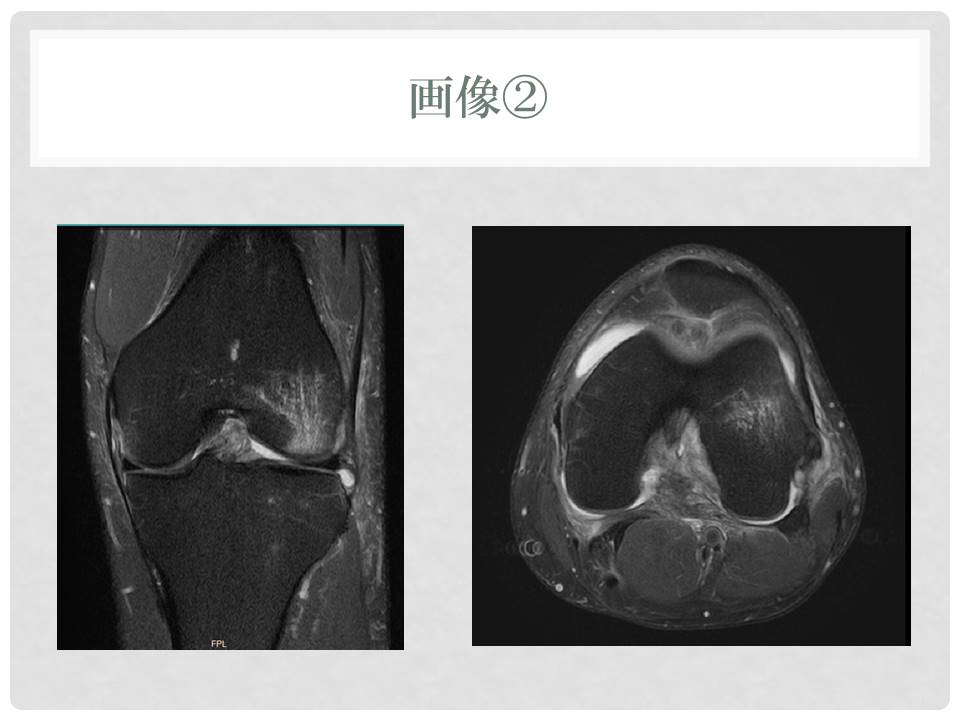

医療機関によるレントゲンなどの画像診断は済んでいます

スライド7